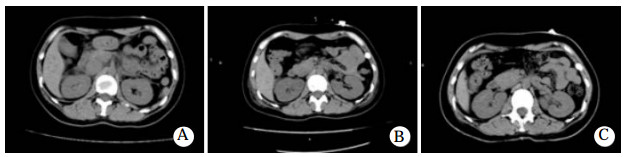

患者入院后,予心电监护,测血压并积极补液、导泻、利尿等对症治疗,但患者拒绝血液灌流治疗。入院10余个小时后,患者出现了胸闷咳嗽,氧饱和度下降至90%,予鼻导管吸氧后经皮氧分压维持在95%左右,入院1 d后氧饱和度降至88.4%,查肌钙蛋白0.136 ng/mL,B型脑钠肽为575.9 pg/mL,均为轻度升高。复查胸部CT出现两肺肺水肿和双侧少量积液(图 1B),查腹部CT亦发现胆囊窝区、胰周渗出改变,腹腔积液(图 2A)。血压进一步降至58/42 mmHg,予多巴胺10μg/(kg·min)收缩血管升压,持续输注葡萄糖酸钙(10 mL/12 h)对抗硝苯地平的钙拮抗剂作用,人血白蛋白(10 g/12 h)补充胶体渗透压,葡萄糖生理盐水(500 mL qd)补液,甲泼尼龙(40 mg/d)抗炎,还原型谷胱甘肽(2.4 g/d)护肝,托拉塞米(20 mg/d)利尿等治疗处理。多巴胺升压使用2 d后转用去甲肾上腺素(8 mg为泵注射)继续使用2 d,药物维持下血压可达(102~122)/(52~68)mmHg。入院4 d,撤去升血压药物后,收缩压能够维持在90 mmHg以上并动态监护未再出现低血压。入院第四天复查胸部CT提示两侧胸腔积液增多(图 1C),腹部CT提示胰周渗出减少(图 2B),继续当前治疗。入院第七天胸腔积液、肺水肿以及腹腔积液几乎完全吸收(图 1D、图 2C)。经过12 d的治疗后患者胸闷气促、咳嗽咳痰完全好转。出院一个月后随访患者未再服用硝苯地平,也未出现上述不良症状。

| 图 2 患者腹部CT(A:入院第1天;B:入院第4天;C:入院第7天) |